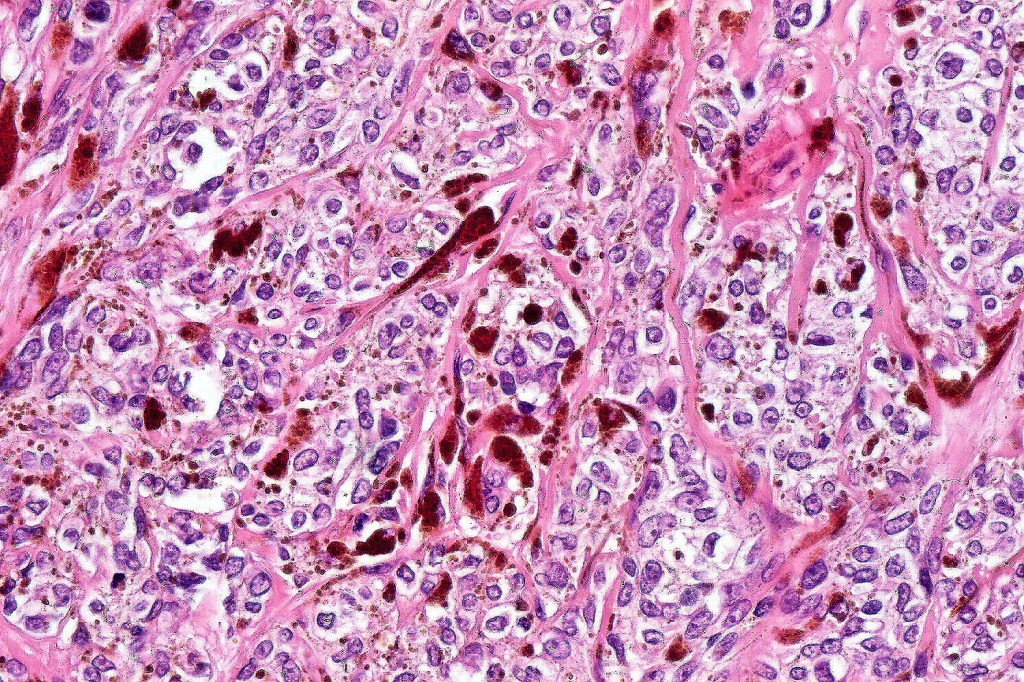

•Admixture of spindle cells, pigmented bipolar or dendritic cells & melanophages

•Cytoplasm is pale and nuclei are small with inconspicuous nucleoli

•An alveolar pattern is characteristic particularly with clear cell nodules

•Stromal fibrosis, myxoid change, vascular hyalinization with cyst formation are often seen

•Some tumors are composed spindle cells in a fascicular or neuronevoid pattern